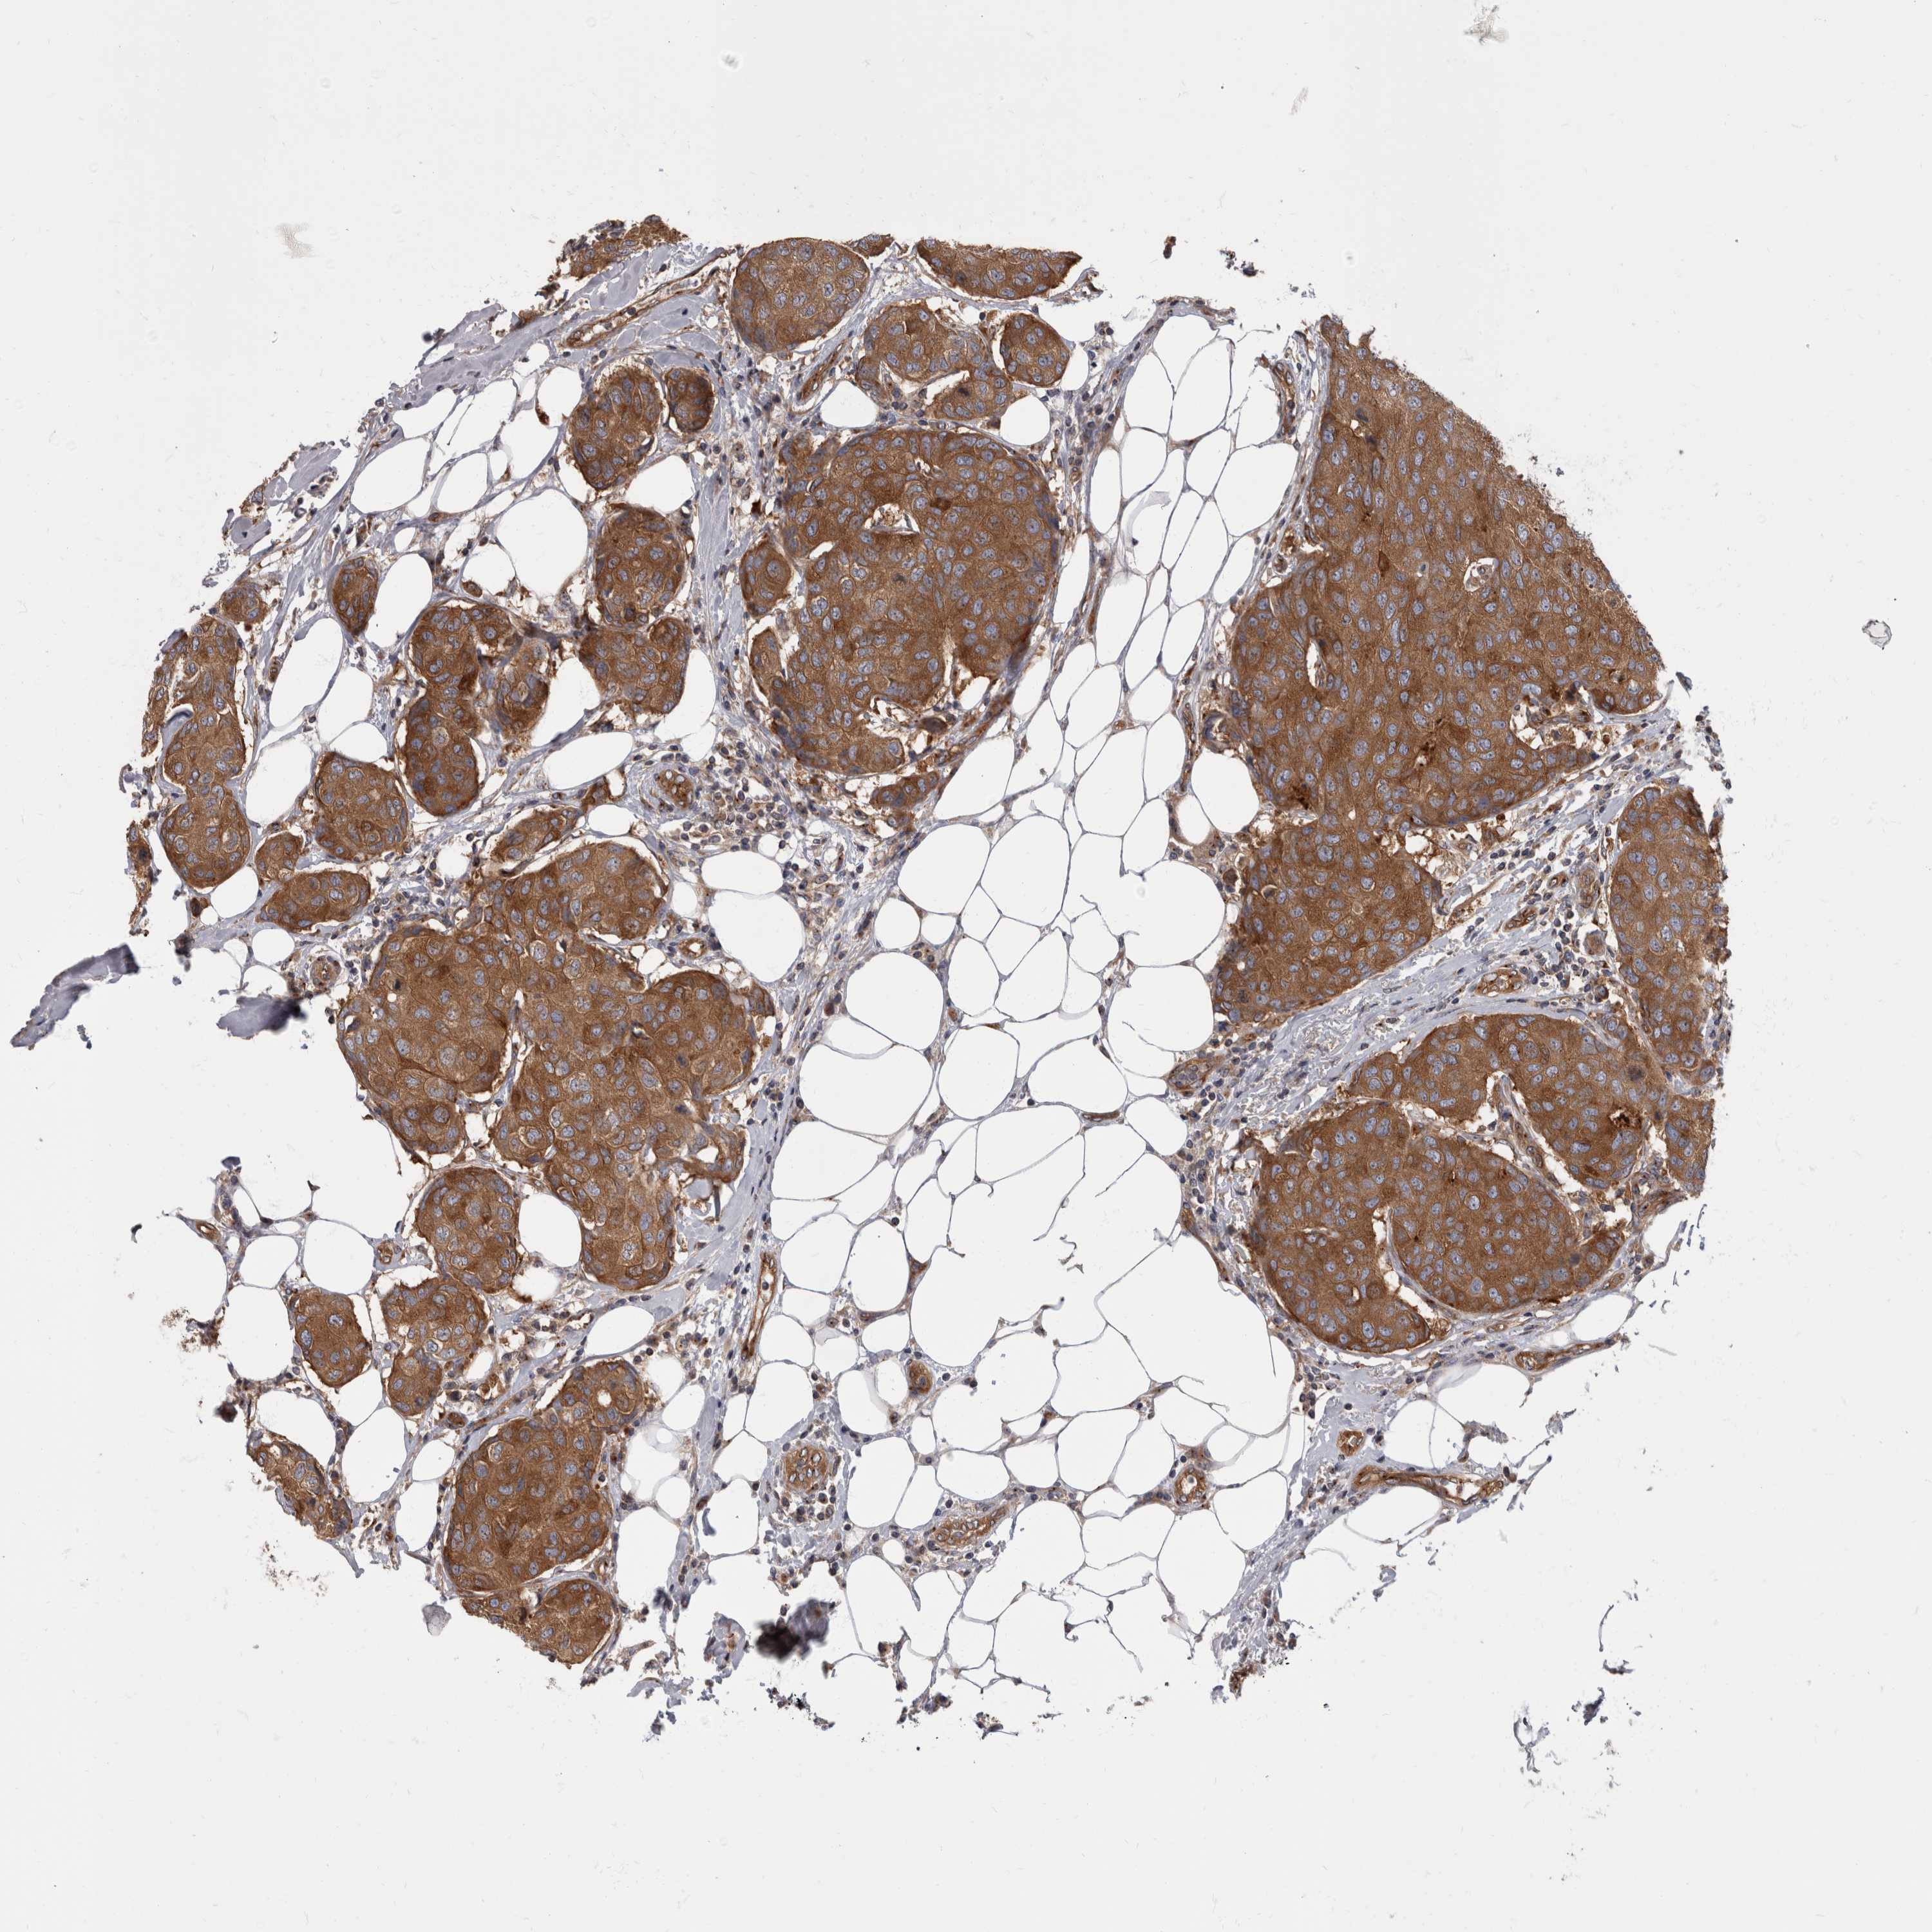

CANCER BREAST CANCER Show tissue menu

BRCA TCGA BRCA VALIDATION PROTEIN EXPRESSION